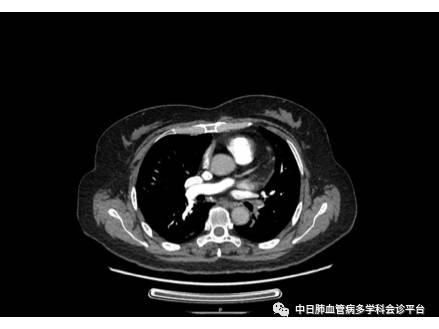

患者既往明确诊断为肺栓塞,再次出现呼吸困难的原因,需考虑肺栓塞复发、慢性血栓栓塞性肺动脉高压(CTEPH)。完善CTPA后发现左肺下叶慢性肺栓塞,右肺中叶动脉闭塞;肺动脉增宽;双肺马赛克征。患者抗凝治疗期间定期监测凝血,INR达标率高,但其曾停止抗凝一个月,后再次出现呼吸困难,需警惕肺栓塞复发,然而并没有D-二聚体升高、影像学新发血栓等证据,CTPA未见新发血栓征象,不支持肺栓塞复发诊断,结合CTPA慢性血栓栓塞征象及肺动脉增宽、外院超声提示肺动脉压力升高,考虑其诊断为CTEPH,这也正是患者再次出现呼吸困难的原因。CTEPH的诊断需要以下条件:1.规范抗凝至少3个月;2.影像学证实肺动脉多发慢性、机化血栓;3.右心导管测得mPAP≥25 mmHg,肺动脉楔压≤15 mmHg,肺血管阻力>3 Wood单位。因此为了进一步明确诊断并评估病情,我们建议患者完善右心导管+肺动脉造影检查,并进一步评估是否可行肺动脉内膜血栓剥脱术治疗,患者表示数月后愿意再次入院评估。治疗上,继续给予华法林抗凝,根据INR调节华法林剂量,并建议患者家庭氧疗;鉴于患者尚未完善右心导管+肺动脉造影检查,且活动耐量较好,无右心衰表现,暂不加用靶向、利尿等治疗。